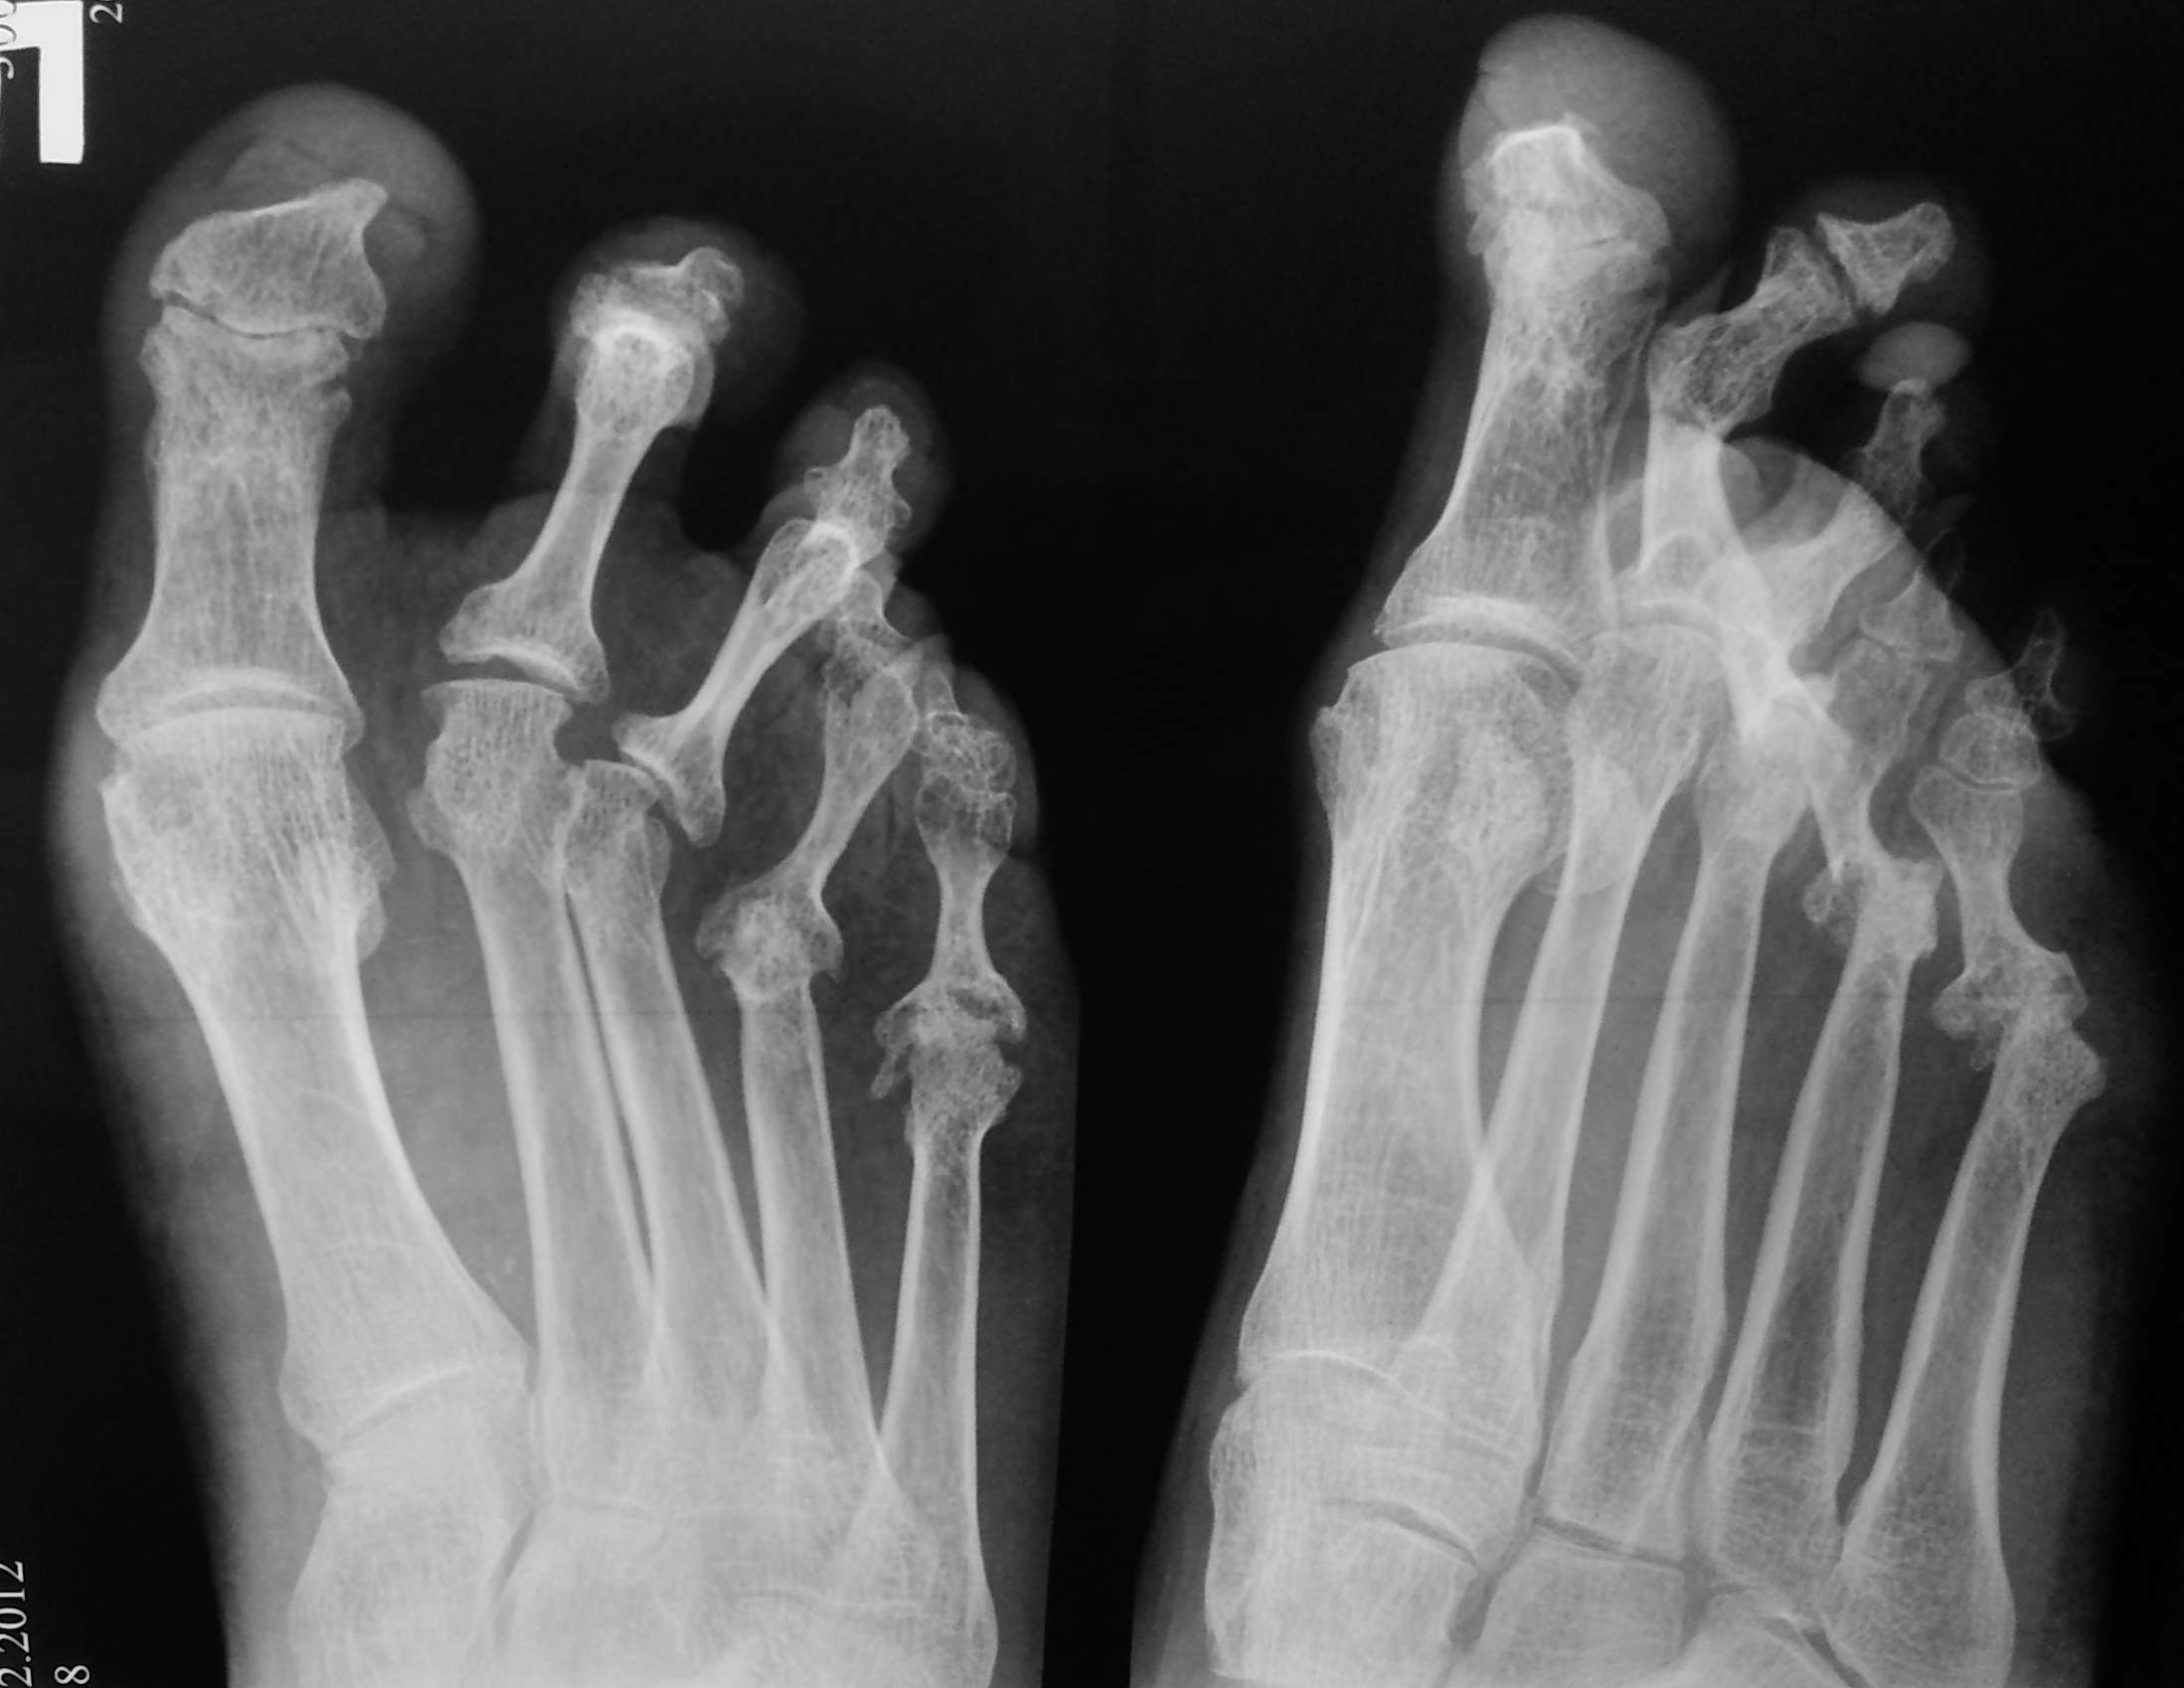

продолжение темы http://weborto.net/forum/1356148170/index_html Послеоперационные снимки (извините за качество), выполнены: Weil - 2,3, резекция головки - 3, резекция проксимальных м/ф суставов(костный анкилоз). Действительно, в первом пальце есть переразгибание, но - не ригидное, пациент на нем вмешиваться отказался. В приложении - предоп рентген в качестве получше и постоп (еще раз сожалею за качество, постараюсь позже выслать получше) Спасибо за советы, надеюсь пригодились.